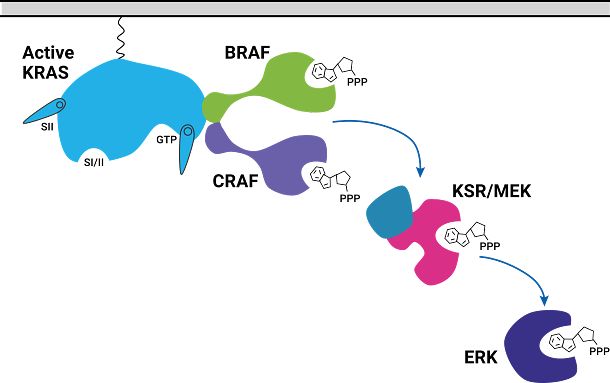

Studying KRAS Protein:Protein Interactions

To better understand CRAF, two domains were selected. The RBD (Ras Binding Domain) and CRD (Cysteine Rich Domain) of CRAF were chosen because of their high basal BRET signal when interacting with KRAS. HeLa cells were bulk transfected with NanoLuc-KRAS(G12D) and CRAF-RBD-CRD-HaloTag expressed from a bidirectional promoter (BiBRET), providing consistent long-term interactions between the two proteins.

KRAS Inhibition with MRTX-1133

To investigate the KRAS-CRAF interaction, a selective KRAS(G12D) inhibitor (MRTX-1133) was utilized. MRTX-1133 is a potent inhibitor known for its specificity to the KRAS(G12D) mutation, without affecting the expression of the KRAS protein itself2. To initially quantify the effect of MRTX-1133 on KRAS activity, we generated a dose-response curve on the GloMax Discover (Figure 4). A BRET ratio was calculated by taking the acceptor signal and dividing it by the donor signal. A clear reduction in the BRET ratio was observed over a three-hour period, with an IC50 of approximately 1.4nM, confirming the potency of the inhibitor.